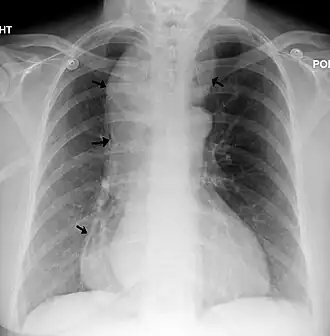

| Raio X de um esôfago amplamente dilatado. | |